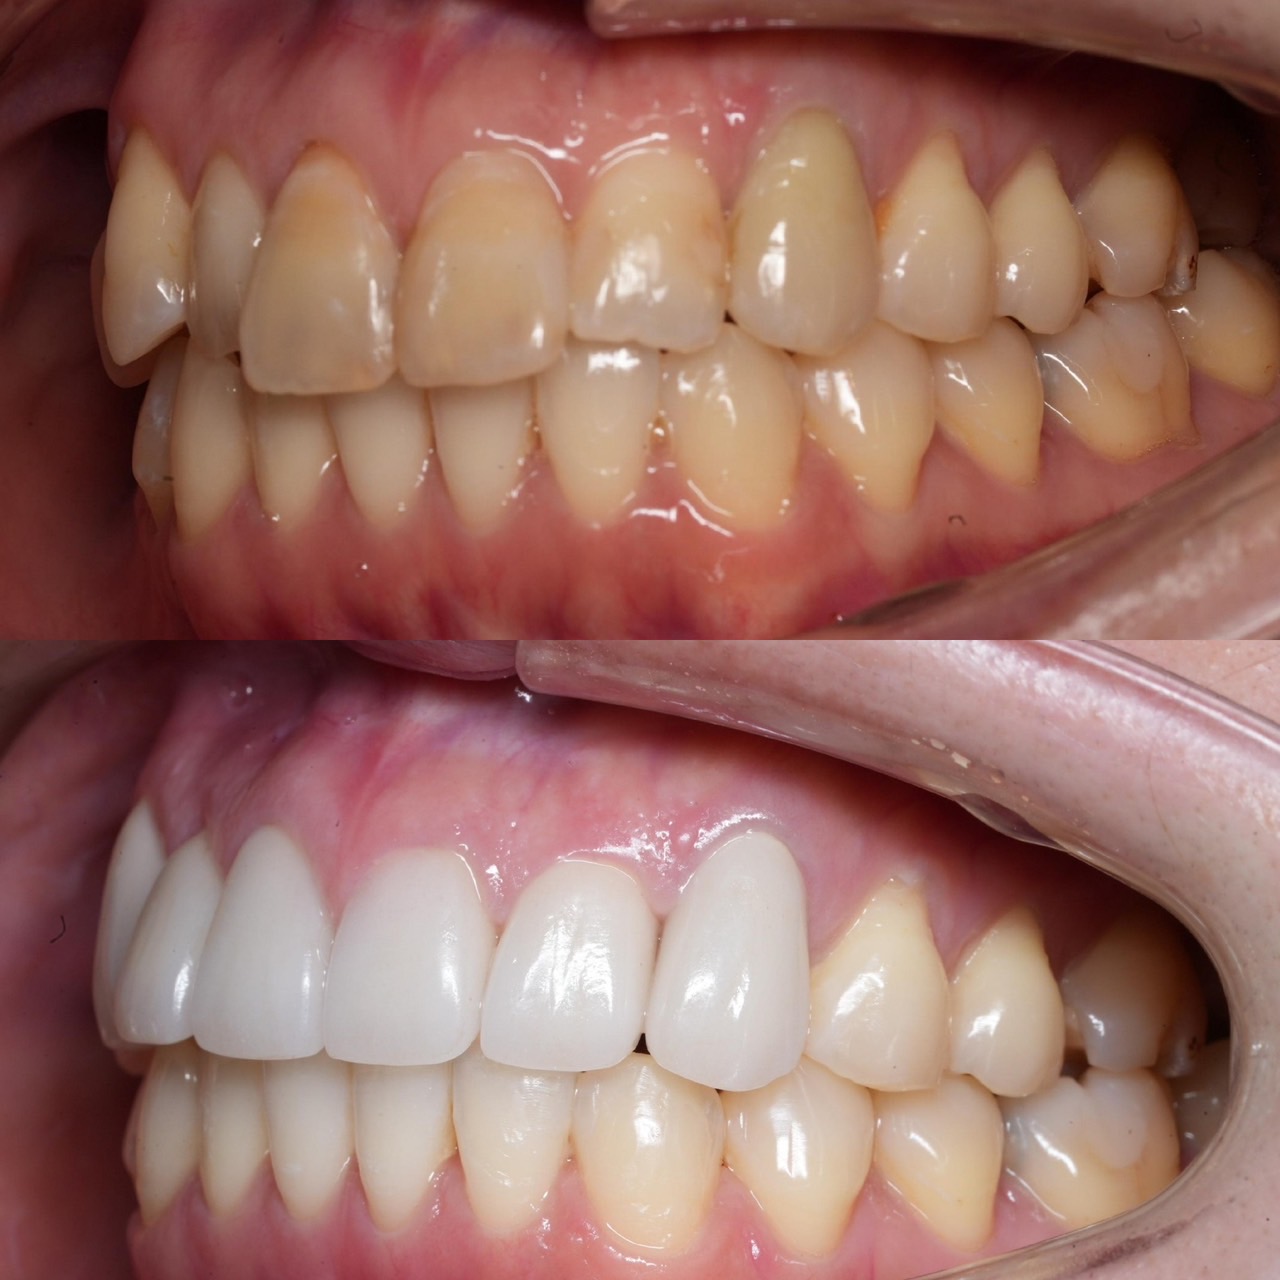

Case031

前歯が虫歯なのと、保険のプラスチックで大きく治療されていて色が悪いこと、歯並びが出っ歯気味であることを気にしてセラミックにしたいという主訴で来院された患者様です。

虫歯が大きかったところは神経治療をきちんと行い、

初診時を含めてトータル4回のご来院で完了です。

今回は前歯を下げる、歯列を整える、白すぎず自然に綺麗に見える色というご希望に沿って治療しました。

ご興味のある方はいつでもご相談ください。

担当 理事長 佐藤 悠野